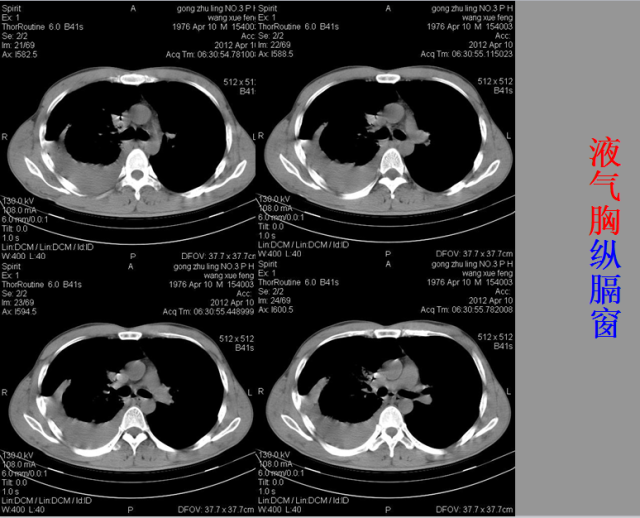

急胸症篇

04